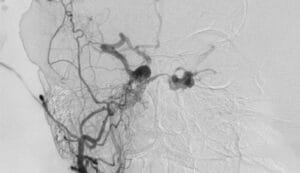

Doğru teşhis koymak yüksek teknoloji kullanımı gerektirir. İlk aşamada genellikle beyin MR tetkiki yapılır. Ancak MR cihazları küçük damar kusurlarını kaçırabilir. Bu nedenle dijital subtraksiyon anjiyografisi (DSA) devreye girer. DSA tetkiki damar yapısını saniye saniye yansıtır. Nitekim bu yöntem tanı koymada altın standarttır. İşlem sırasında damara özel kontrast madde verilir. Böylece kan akış hızı net şekilde ölçülür.

Anjiyo işlemi genellikle kasık bölgesinden gerçekleştirilir. İnce kateterler yardımıyla beyin damar sistemine girilir. Hastalar bu süreçte genellikle hiçbir acı duymaz. Sonuç olarak fistülün tam koordinatları başarıyla belirlenir. Ayrıca besleyici atardamarların sayısı tam olarak saptanır. Bu kritik bilgiler tedavi planı için elzemdir. Cerrahımız anjiyo sonuçlarını bizzat en ince ayrıntısına kadar inceler. Modern teknoloji sayesinde hata payı tamamen yok edilir.

Tanı sonrasında hastanın risk grubu belirlenir. Kanın beyin dokusuna kaçış hızı büyük önem taşır. Eğer kaçış fazlaysa kanama riski çok yüksektir. Bu durumda tedaviye derhal başlanması gerekir. Nitekim bilimsel verilere ışığında en güvenli yol seçilir. Teşhis aşamasındaki titizlik operasyon başarısını doğrudan belirler.

BT anjiyo yöntemi de bazen yardımcı olur. Ancak kesin karar için DSA vazgeçilmezdir. Nitekim damar haritası sadece DSA ile netleşir. Uzman ekibimiz görüntüleme sürecini yakından yönetir. Doğru veri doğru tedavi sonucunu getirir. Sağlığınız için en gelişmiş yöntemleri kullanıyoruz.